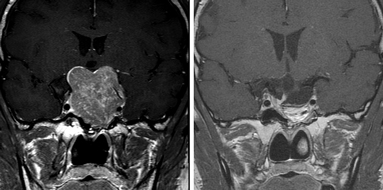

経鼻内視鏡手術の術前と術後

当院では、手術の最初から最後まで内視鏡で行う、内視鏡単独経鼻手術を得意としています。鼻内を内視鏡で操作することで鼻への負担を最小限とし、また腫瘍摘出から摘出後の閉鎖まで内視鏡で行うことで広い範囲を目視で観察しながら手術ができるため安全な操作が行えます。そのため手術による死亡例もしくは意識障害や麻痺などの重篤な合併症例は皆無です。また、摘出後のトルコ鞍閉鎖に硬膜縫合という特殊な手技を行うことができるため、この手術の大きな合併症である髄液漏の危険性を0.4%に抑えることができています。